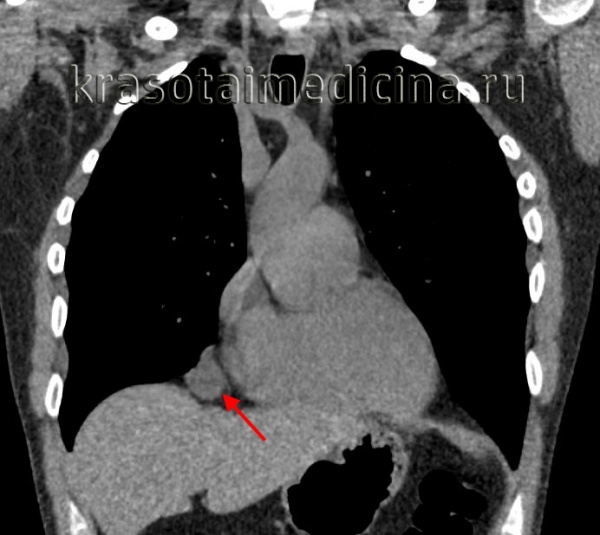

Тератомы средостения обычно располагаются в переднем средостении, рядом с крупными сосудами и перикардом. Долгое время никак не проявляются. Обычно начинают расти в подростковом возрасте или в период гестации. Могут увеличиваться до 20-25 см. Сдавливают легкие, сердце, плевру и кровеносные сосуды. Сдавление внутренних органов сопровождается учащением сердцебиения, болями в сердце, одышкой и кашлем. При прорыве тератомы средостения в бронх или плевральную полость возникает синюшность кожи, удушье, повышение температуры тела, асимметрия грудной клетки, икота, иррадиирующие боли в области надплечья на стороне поражения. Возможно легочное кровотечение и развитие аспирационной пневмонии.

Для выявления крестцово-копчиковых тератом ведущую роль играет адекватное обследование плода в период внутриутробного развития. Диагноз обычно выставляют по результатам акушерского УЗИ. В остальных случаях диагностику осуществляют на основании жалоб, данных объективного осмотра, лабораторных и инструментальных исследований. При тератомах средостения и крестцово-копчиковых новообразованиях назначают обзорную рентгенографию, при необходимости проводят рентгенконтрастные исследования и ангиографию.

Высокоинформативным способом диагностики тератом является КТ пораженной области. Методика позволяет определить форму, размер и строение опухоли, а также оценить ее взаимосвязь с другими анатомическими структурами. При подозрении на наличие метастазов назначают КТ, МРТ, рентгенографию грудной клетки, сцинтиграфию и другие исследования. В качестве уточняющего метода применяют анализ крови на хорионический гонадотропин и альфа-фетопротеин. Окончательный диагноз выставляют с учетом результатов пункционной биопсии и последующего микроскопического исследования материала.

Кистозные тератомы содержат в своей структуре элементы эктодермы и возникают в процессе нарушения эмбриогенеза. В медицине встречаются дермоидные кисты яичников, брюшной стенки, кожи, забрюшинной клетчатки, печени, почек и др. органов и тканей. Дермоидные кисты обычно расположены в передневерхнем отделе средостения. Величина дермоидных кист средостения может достигать 15-25 см. Форма кистозных тератом обычно неправильная овальная; консистенция эластическая или мягкая. Стенки кисты могут содержать хрящевые и известковые включения. Внутри кисты заключена густая кашицеобразная жирная масса с множеством различных включений (волос, чешуек эпидермиса, кристаллов холестерина, аморфных жиров, зубов).

Более чем в половине случаев дермоидная киста средостения сопровождается различными сердечно-сосудистыми нарушениями: приступами стенокардии, болью в области сердца, тахикардией. У 30% больных признаком дермоидной кисты средостения служит появление продуктивного кашля с выделением кашицеобразной массы, содержащей примесь волос и жира, что наблюдается при прорыве кисты в бронх. У части пациентов отмечается выпячивание грудной стенки в проекции расположения опухоли.